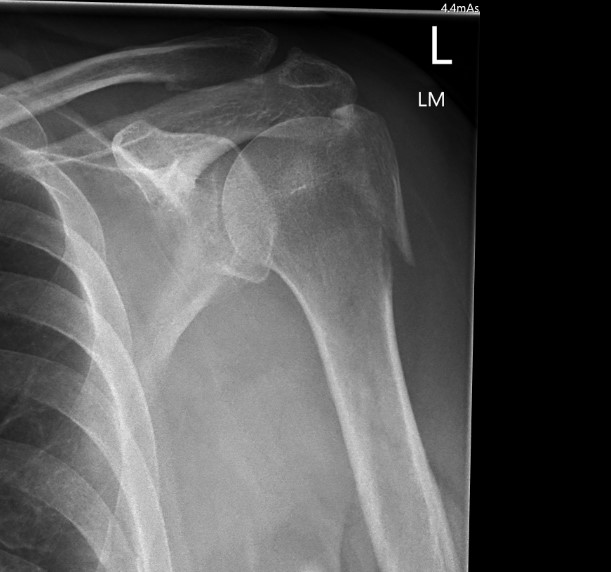

proximal humerus fracture Background ORIF with locking plate Arthroplasty Greater tuberosity fractures Lesser tuberosity fractures / avulsions Book traversal links for Proximal humerus fractures ‹ Pectoralis Major Tears Up Background ›